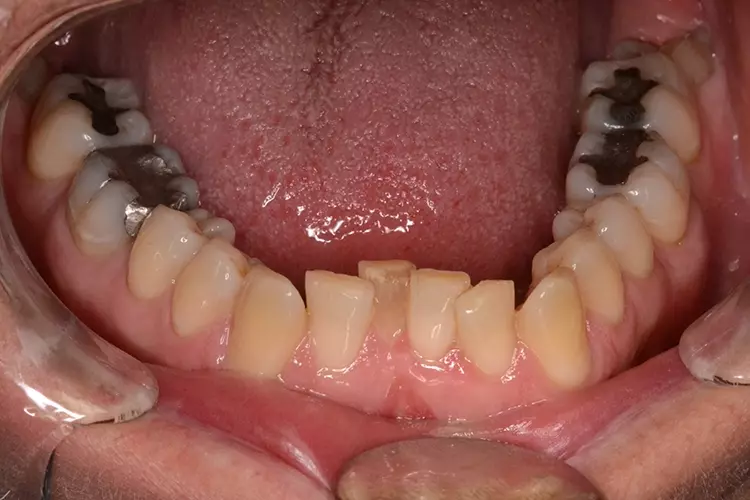

Neugestaltung der Front bei starken Zahnfehlstellungen

Bei dem heute 49-jährigen Patienten wurde seit Kindertagen versäumt, die Ober- und Unterkieferzahnbögen kieferorthopädisch auszurichten. Der Patient leidet seitdem stark unter seinen Zahnfehlstellungen.

Die Fraktur des stark elongierten Zahnes 21 war für den Patienten der Ausgangspunkt, sowohl die Front des Ober- als auch des Unterkiefers prothetisch überarbeiten zu lassen. Dabei wurde der frakturierte Zahn 21 durch ein navigiert eingesetztes Sofortimplantat ersetzt, während die verschachtelt stehenden Zähne 12 und 42 durch eine Brückenversorgung korrigiert wurden (Abb. 4a-j).